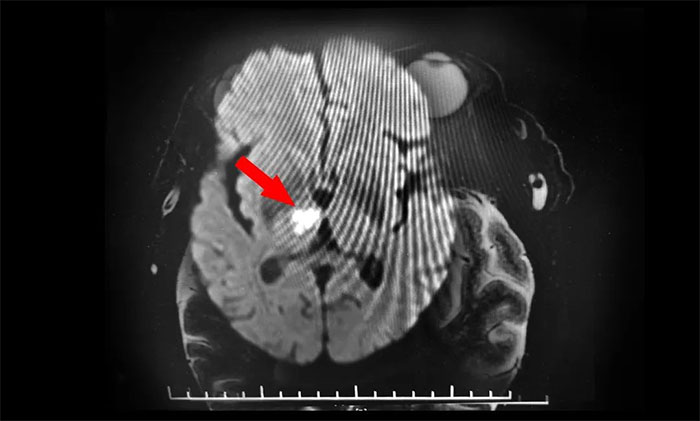

再次行MR頭顱MRI平掃+增強(qiáng)+DWI+MRA,提示腦干、右側(cè)丘腦及雙側(cè)大腦半球白質(zhì)多發(fā)梗塞灶及缺血灶(中腦及右側(cè)丘腦梗塞急性期),右側(cè)大腦后動(dòng)脈狹窄,右MCA-M1段狹窄。至此,該患者雙側(cè)動(dòng)眼神經(jīng)損傷原因診斷明確,病因?yàn)橛覀?cè)中腦梗死所致,責(zé)任血管為右PCA-P1的狹窄致中腦旁正中動(dòng)脈閉塞,為動(dòng)眼紅核綜合征,導(dǎo)致同側(cè)動(dòng)眼神經(jīng)麻痹伴對(duì)側(cè)肢體共濟(jì)失調(diào),同時(shí)累及右丘腦旁正中動(dòng)脈。

▲ DWI確診腦干梗死

張靜波主任指出,DWI是診斷急性腦梗死的有力武器,但是每個(gè)人的腦血管側(cè)支循環(huán)不同,DWI沒(méi)有固定的顯影時(shí)間,特別是對(duì)于后循環(huán)的腦梗死,DWI更容易出現(xiàn)陰性,這些都給診斷增加了難度。